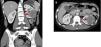

El examen patológico reveló un tumor encapsulado de 5,5 x 4,5 cm, de aspecto hemorrágico, con áreas fibrosas de color blanquecino. Microscópicamente la lesión tumoral se encontró constituida por células de mediano tamaño, con núcleos medianos, vesiculosos, con cromatina irregular, algunas con nucléolo inconspicuo y citoplasma eosinófilo, otras con citoplasma claro, dispuestas en un patrón difuso con extensa hemorragia y leve infiltrado inflamatorio mononuclear (figura 2 A y figura 2 B), sin invasión de la cápsula renal. No se encontró atipia celular, mitosis, ni necrosis. Las células tumorales fueron positivas para vimentina y mostraron una positividad fuerte y difusa para CD34 (figura 2 C). La observación a nivel ultraestructural permitió reconocer células con gránulos intracitoplasmáticos con diferentes grados de electrolucidez, rodeados por membranas. En cuanto a la morfología, variaron de redondos a alongados, adquiriendo algunas formas con bordes rectilíneos, y se destacó en algunos de ellos una forma romboidal cristaloide que a grandes magnificaciones presenta una estructura de zigzag de marcada electrodensidad (figura 2 D). Hallazgos vinculables a tumor de células yuxtaglomerulares (TCY), permitiendo corroborar la sospecha clínica.

Figura 2.